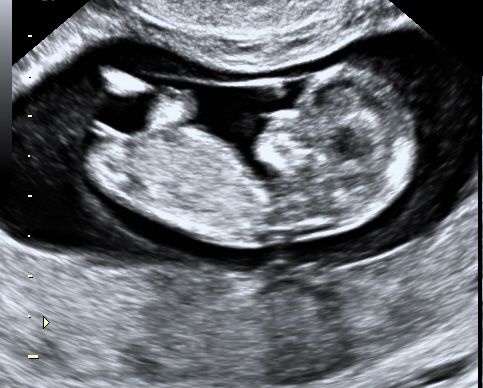

Буду мамой пятерых, вот фото примерно 10-11 недель Изображение

Анна, по этому фото девочка

Анна, девочка 😊 У мальчиков бугорок торчит.